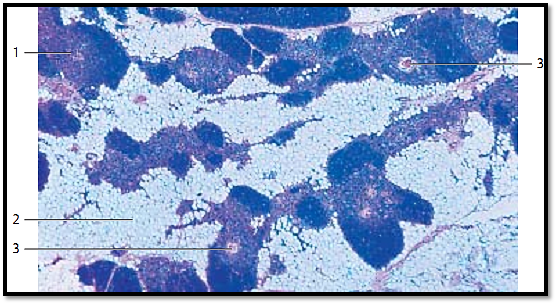

Thymus

The thymus is derived from the pharyngeal pouch. In relationship with other lymphatic organs, it takes a central, superordinate place. In a histological cross-section, the infantile thymus is seemingly built of lobes. Each lobule consists of a corte x 1 (stained blue-violet), which is rich in lymphocytes, and the medulla (stained lighter and reddish) with lower cell density 2 . Vascularized connective tissue 3 , 4 fills the spaces between lobules. It also pushes into the organ, up to the border between cortex and medulla, forming septa (trabeculae). Meshwork s of reticulum cells (epithelial reticulum cells, lymphoepithelial organ ), not fibers, form the supportive structures for cortex and medulla. The reticular cells have arisen from entodermal epithelium. Small lymphocytes (T-lymphocytes) pre dominate underneath the cortex. The medulla contains mostly lymphoblasts, lymphocytes and epithelial reticulum cells. The thymus also contains mast cells, macrophages and interdigitating dendritic cells. The literature of ten describes six different types of epithelial cells. Lymph follicles with germinal centers do not exist in the thymus.

1 Cortex

2 Medulla

3 Blood vessels

4 Connective tissue

Stain: alum hematoxylin-eosin; magnification: × 10